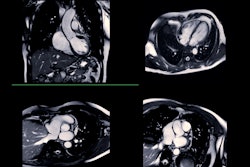

PET/CT can rule out CAV in heart transplant patients